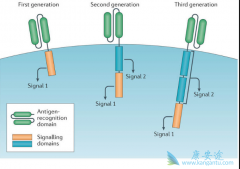

2012年,6岁的急性淋巴细胞白血病小女孩Emily在无药可医的情况下,尝试了Carl June实验室的研究性 CART细胞治疗 ,奇迹至此发生,治疗后她一直健康的生存至今。CD19 CART细胞治疗自此以百米速度进入公众视野和临床实践。其中CAR,即嵌合抗原受体,是该治 ...